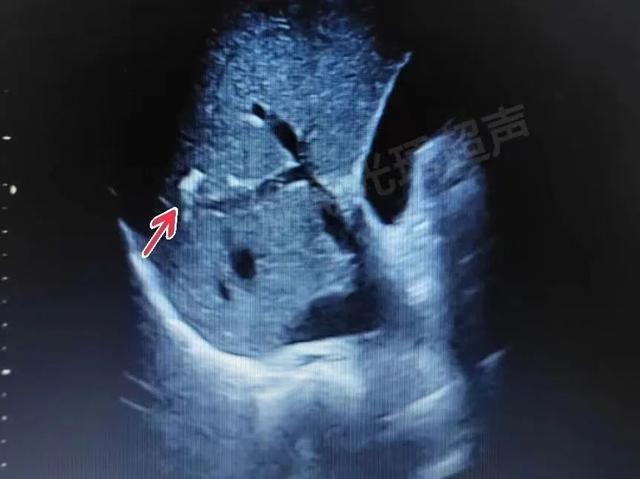

超声下肝内钙化灶典型的特征表现为:肝实质内斑点状、团块状强回声,无肝内外胆管扩张、无伴行肝静脉扩张,多为单发,通常肝右叶多见于肝左叶(如下列图4)。

图1